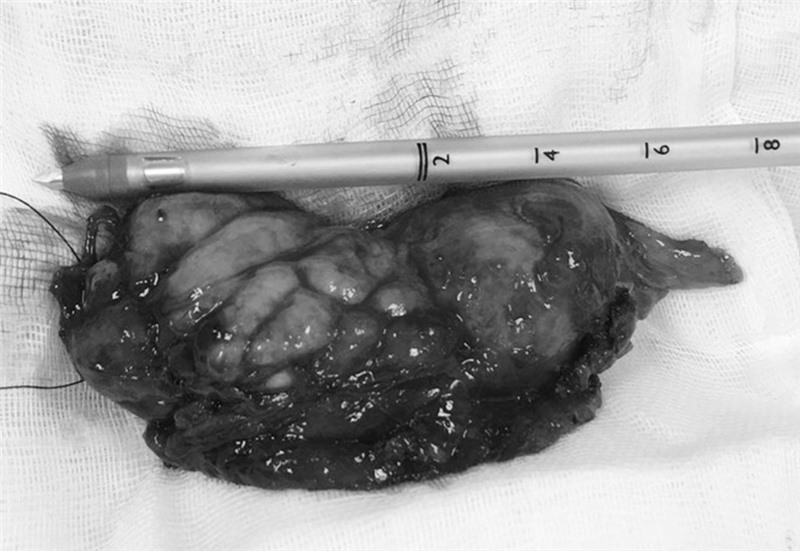

Khối u trung thất trước kích thước 11x5cm sau khi được cắt bỏ.

Các bác sĩ khoa Phẫu thuật - Can thiệp tim mạch & Lồng ngực Bệnh viện cho biết, trường hợp người bệnh M. khối u đã tiến triển ở giai đoạn muộn. Khối u lớn lệch trái, dạng đặc, bờ chia thùy múi, đè, xâm lấn vào màng phổi trái khiến người bệnh ho khan, tức ngực, khó thở. Người bệnh đã được lựa chọn đường mổ ½ giữa xương ức kết hợp mở ngực trái để cắt u và tuyến ức. Với đường mổ này thì phẫu trường rộng rãi đảm bảo lấy được u và tuyến ức triệt để, an toàn, đồng thời giảm thiểu tổn thương xương ức, giúp người bệnh hồi phục sớm sau mổ. Sau 2 giờ phẫu thuật, các bác sĩ đã lấy bỏ thành công khối u và tuyến ức kích thước 11x5cm cho người bệnh, gửi làm giải phẫu bệnh. Kết quả xác định u tuyến ức tuýp B2 giai đoạn Masaoka II, được chỉ định xạ trị tiếp sau mổ.